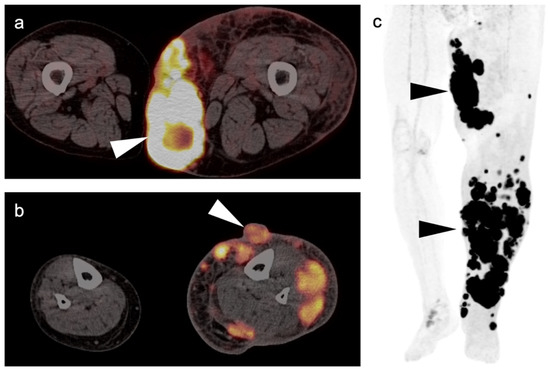

- Umemura, H.; Yamasaki, O.; Kaji, T.; Hamada, T.; Otsuka, M.; Asagoe, K.; Iwatsuki, K. Prognostic value of 18 F-fluorodeoxyglucose positron emission tomography/computed tomography in patients with cutaneous angiosarcoma: A retrospective study of 18 cases. J. Dermatol. 2017, 44, 1046–1049. [Google Scholar] [CrossRef] [Green Version]

- Tokmak, E.; Özkan, E.; Yağcı, S.; Kır, K.M. F18-FDG PET/CT Scanning in Angiosarcoma: Report of Two Cases. Mol. Imaging Radionucl. Ther. 2011, 20, 63–66. [Google Scholar] [CrossRef]